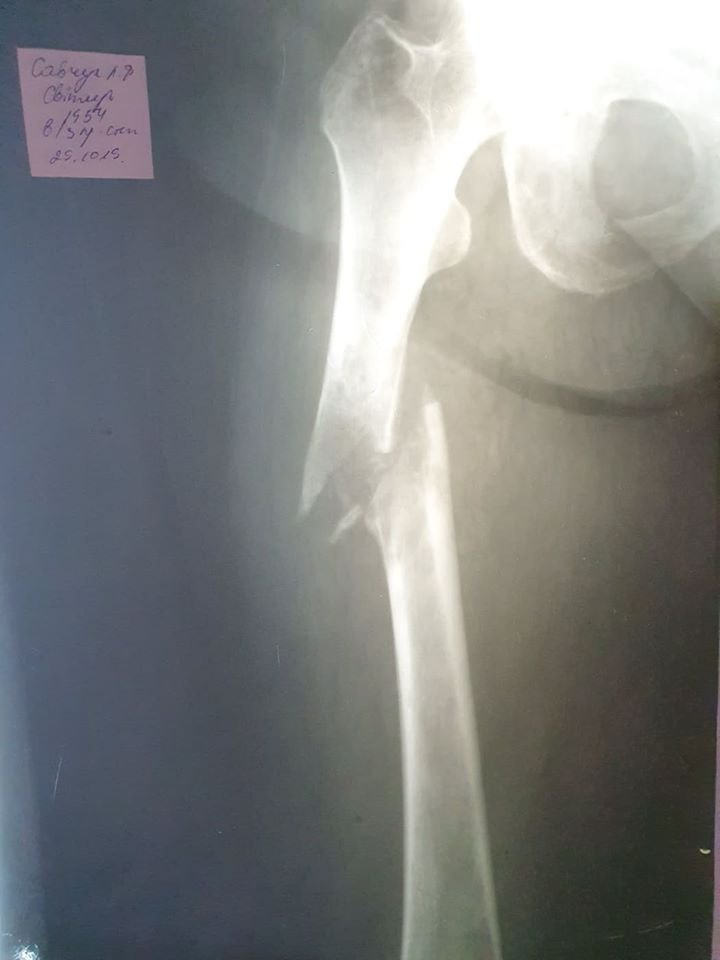

Вперше лікарі-травматологи Любомльської лікарні провели операцію жінці, яка мала онкологію з метастазами в кістках, та отримала патологічний перелом лівої стегнової кістки зі зміщенням.

Ризики для проведення такої операції були чималі, оскільки 64-річна пацієнтка, жителька одного з сіл Шацького району, мала гіпертонічну хворобу, онкологію стегнової кістки та був ризик кровотечі під час операції.

Тривала операція півтори години, під час якої лікарі вправили місце перелому та зафіксували його за допомогою апарату зовнішньої фіксації (зовнішніми металевими штирями).